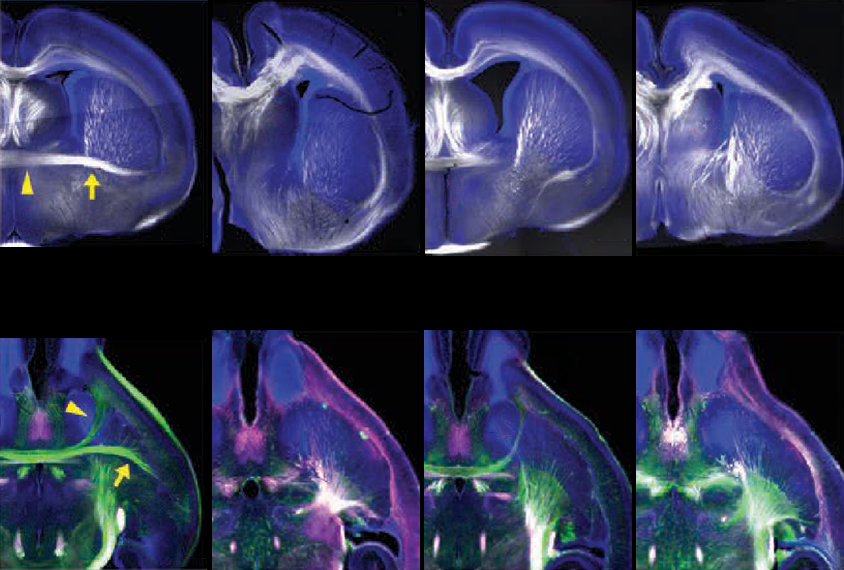

Despite the imbalances, the two types of heterozygous mice displayed similar brain structure changes, including missing sections of the anterior commissure, a white-matter tract that connects the two hemispheres. The same structure is absent in mice lacking one copy of TBR1, leading to social and cognitive problems, and appears to be thin or missing in MRI scans of autistic people with TBR1 variants, according to previous results.

T

he structural changes seem to align with the fact that TBR1 regulates the expression of genes that determine the architecture of the cerebral cortex and the organization of the brain’s outer layers. Both strains of homozygous mice displayed disordered layering, although the heterozygous ones did not, suggesting that one functional copy of TBR1 is sufficient during early cortical development.What’s more, the two homozygous mutants differed in their patterns of cortical disorganization. Those with the frameshift mutation resembled mice that lack TBR1 entirely: Their cortical layers were inverted, with what is typically the deepest layer at the brain’s surface. By contrast, the missense mice showed a more complicated arrangement, suggesting that TBR1 still functions, albeit differently.